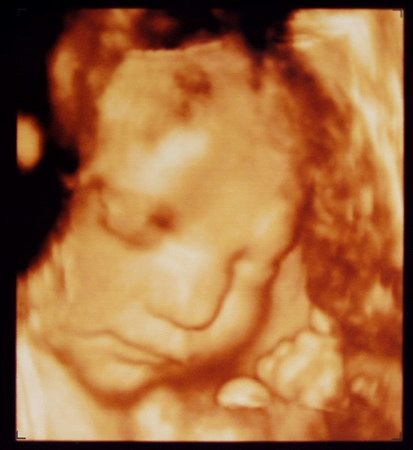

Timi26! Látom jártál a 4d-s topicban :) Beteszem ide is a képet. Elmentünk mégegy 4d-re, mert az utolsó két kórházi uh annyira rossz volt, nekem nem mutattak semmi, fel sem vették, így férjem sem látta és már nagyon hiányunk volt, így hírtelen felindulásból bementünk a Brendonba és milyen jól döntöttünk! Annyira jó volt. Olyan kis husi már és rengeteget mosolygott, ivott, ásítozott, grimaszolt. édes volt nagyon.